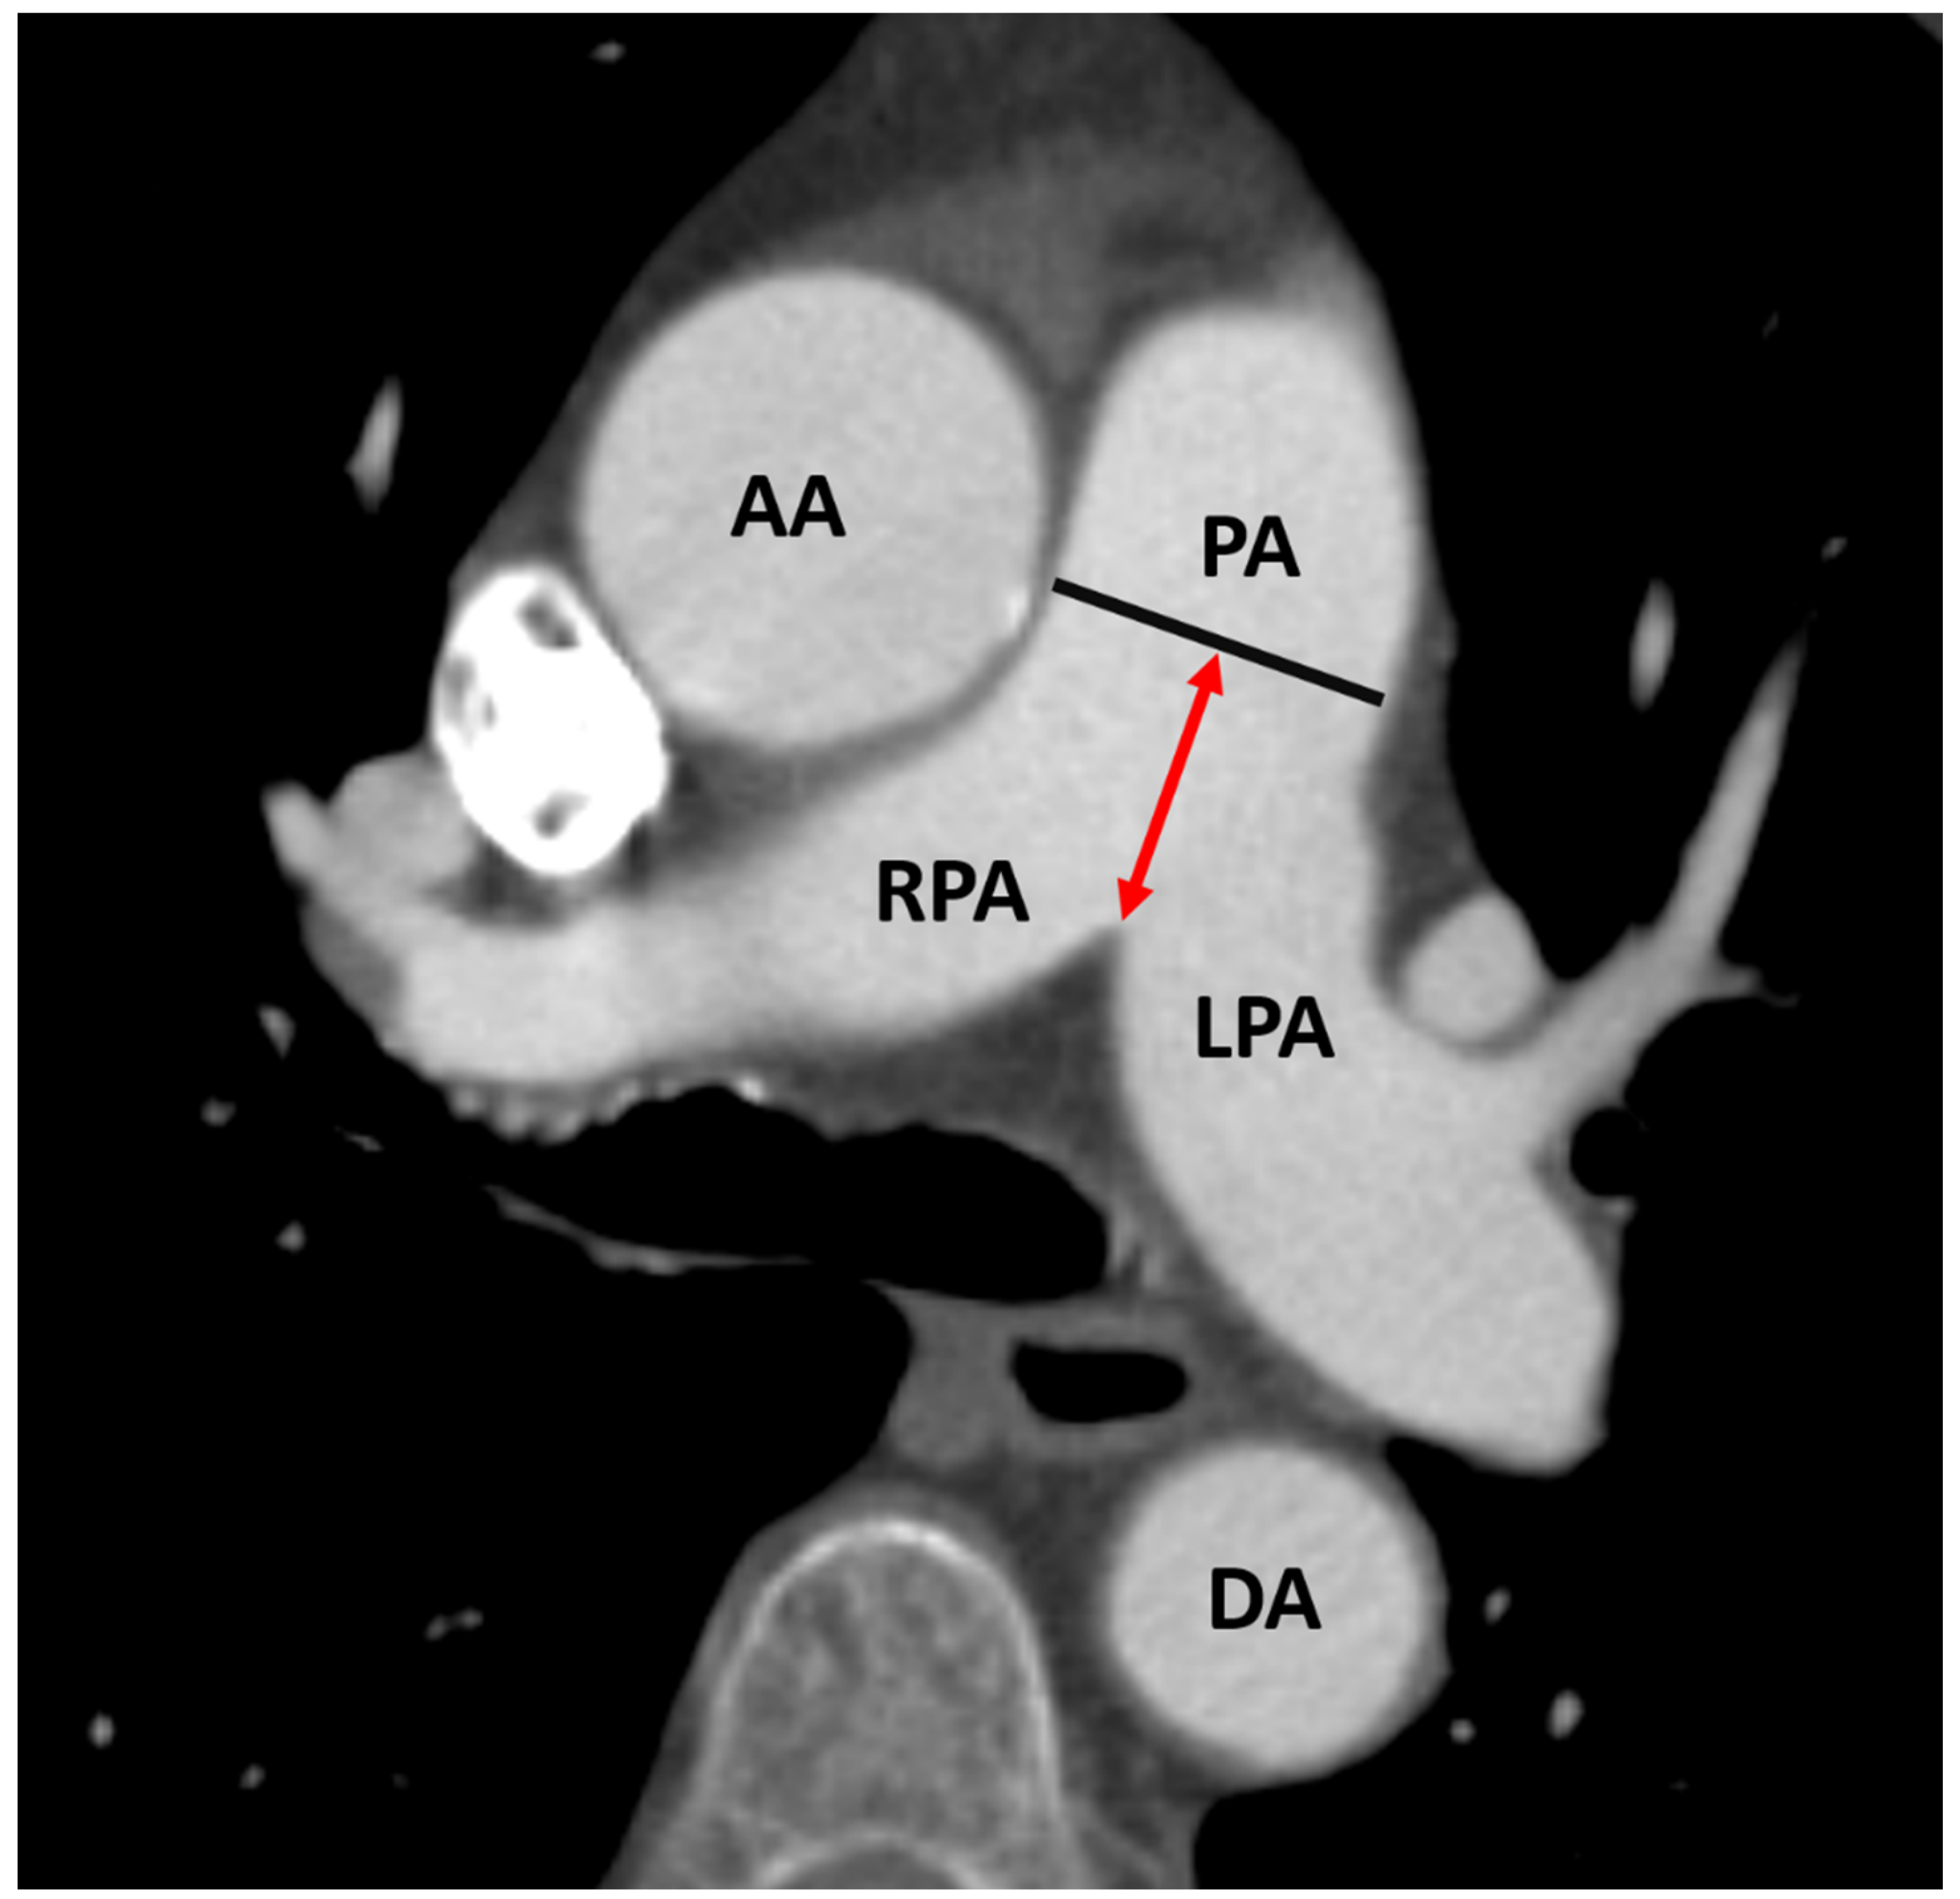

2.3. CTA Protocol and Measurement of PA Diameter for PH Assessment

4.1. Can a PA/BSA ≥ 16.6 mm/m2 Be Used as Evidence for PH?